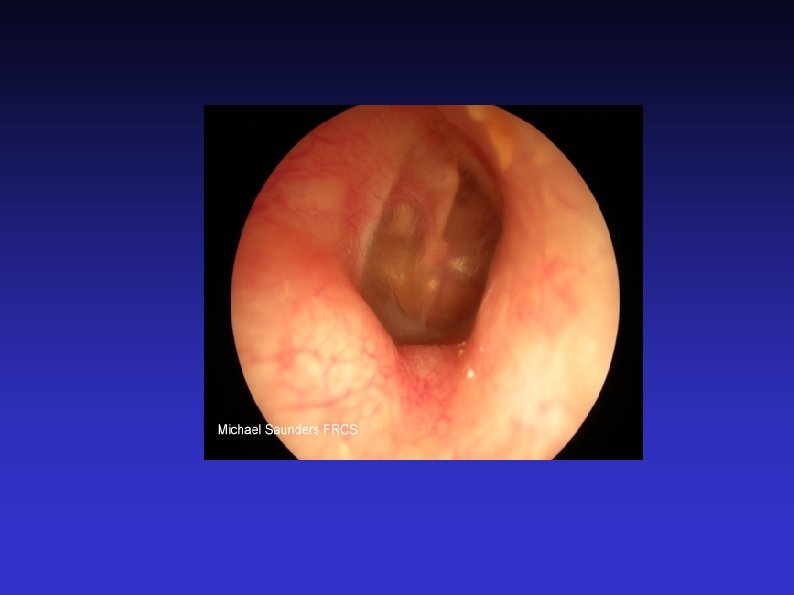

Examination of the Ear 7) Otoscopic examination The lateral process and handle of the malleus lie towards the centre of the tympanic membrane Four quadrants Perforation Central or marginal What can be seen through it Mastoid cavity Dry Wet, inflamed

Examination of the Ear 8) Fistula test A test for ENT doctors! Warn the patient A cholesteatoma has erroded part of a semi-circular canal Pressure in the EAM causes conjugate deviation of the eyes